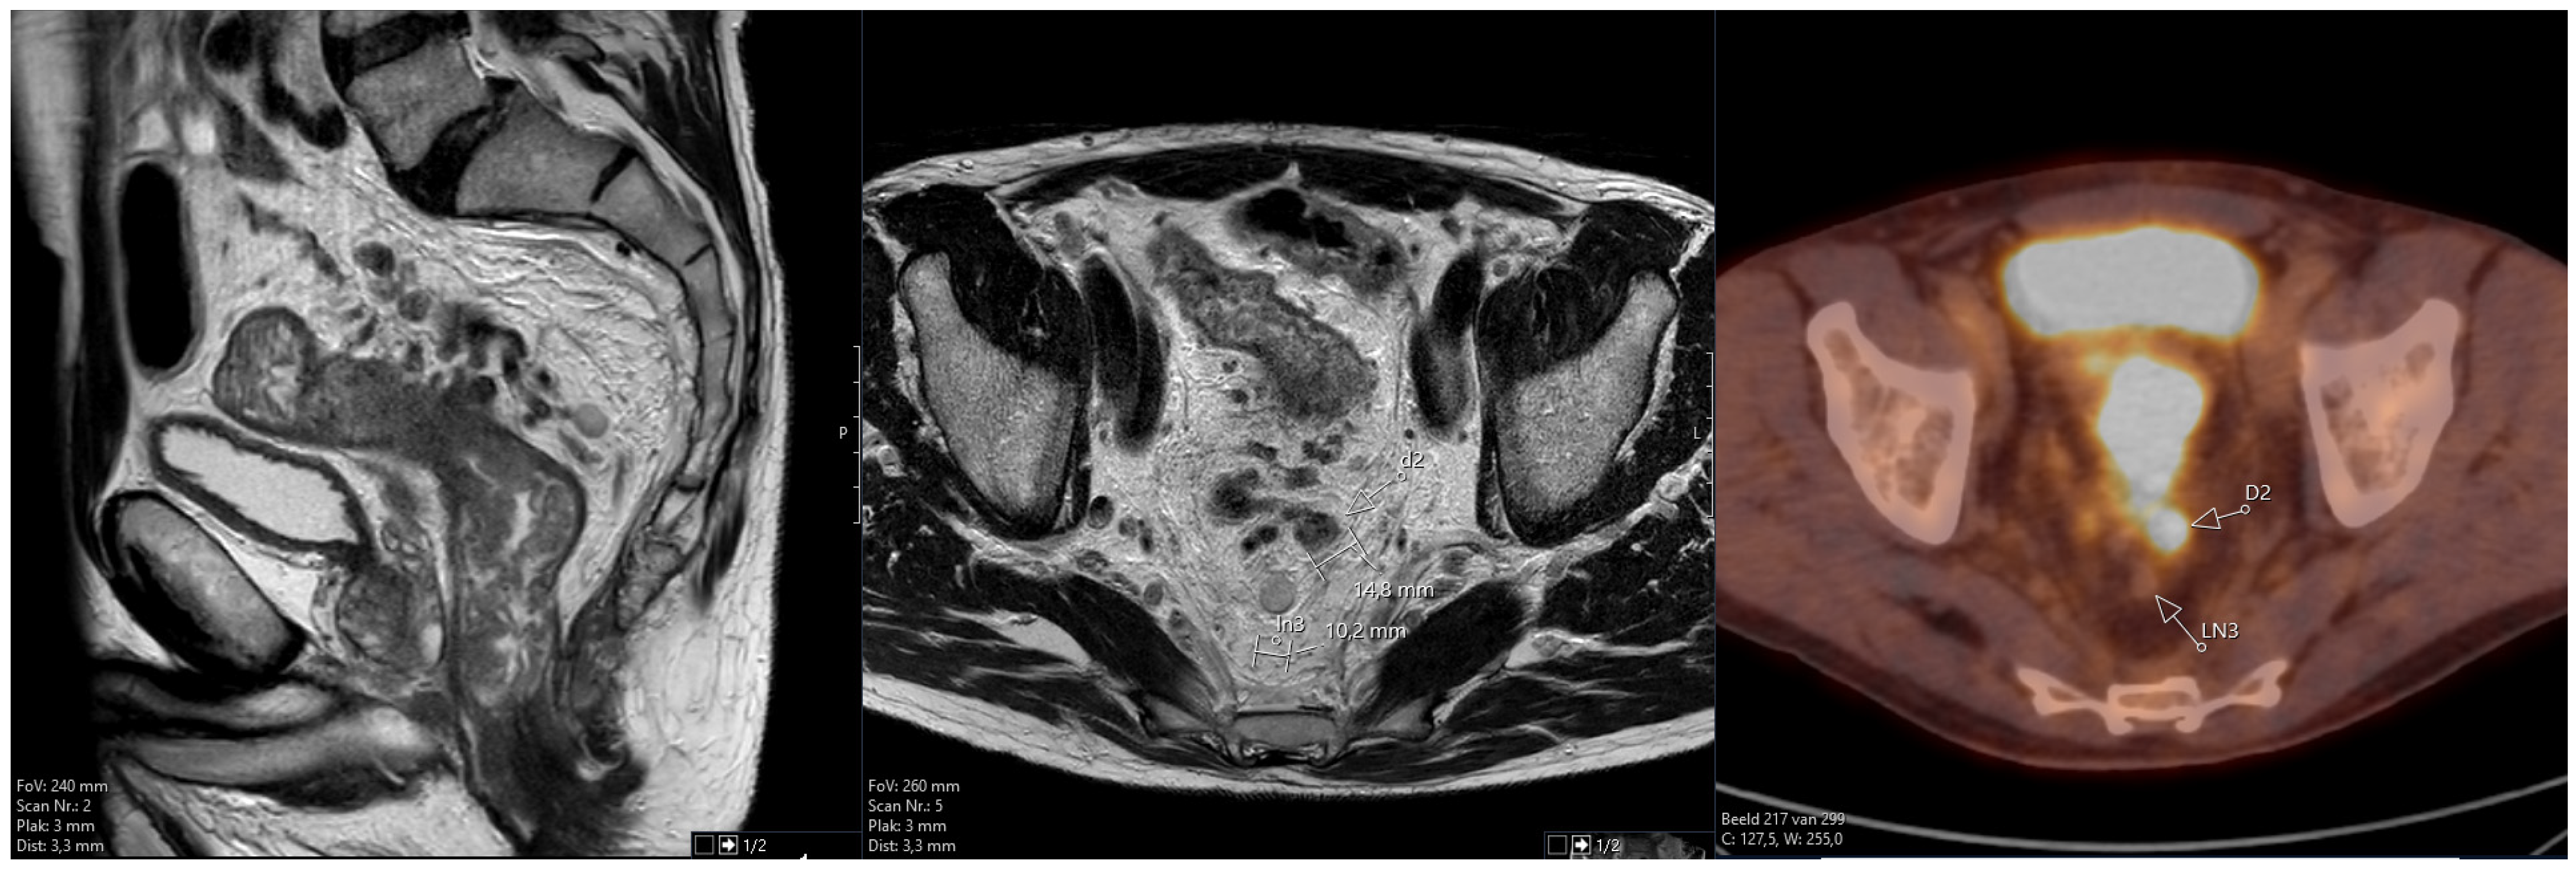

The Additional Role of F18-FDG PET/CT in Characterizing MRI-Diagnosed Tumor Deposits in Locally Advanced Rectal Cancer

2.3.2. F18-FDG PET/CT

2.3.3. Correlating MRI and F18-FDG PET/CT Images